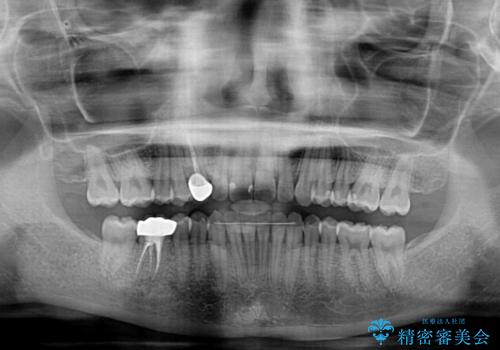

- 下顎の八重歯を気にして来院された患者様です。

マウスピース矯正でもワイヤー矯正でも対応可能であり、マウスピースによる治療を希望されたため、インビザラインを用いることとしました。

下顎前歯にデコボコが集中していたため、顎間ゴムによる後方移動とIPR(歯と歯の間を削ること)により歯列を整えることとしました。

矯正治療途中で右下奥歯の虫歯治療を近医で行ったようで、既に神経が失活していたと合わせて矯正治療後に補綴治療を行う予定です。